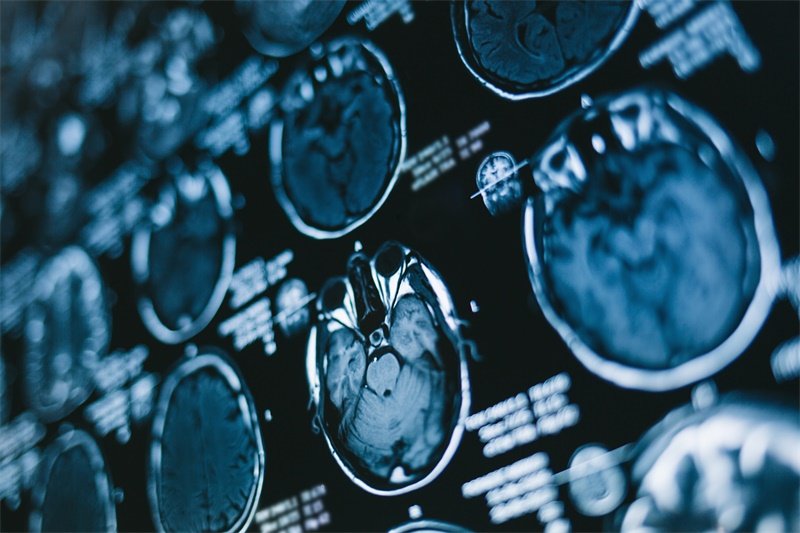

MRI检查

磁共振成像(MRI)是目前对蝶鞍区病变的最佳成像检查方法。它能够提供清晰的软组织图像,帮助医生判断病变性质及对周围结构的影响。